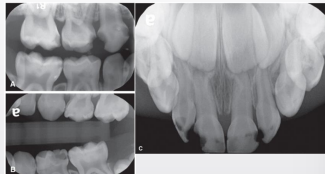

classify this according to radiographic presentation of the ADA

E1

classify this according to radiographic presentation of the ADA

E2

classify this according to radiographic presentation of the ADA

D1

classify this according to radiographic presentation of the ADA

D2

classify this according to radiographic presentation of the ADA

D3

classify this lesion according to the ADA and ICDAS/ICCMS systems

caries within the outer half of the enamel: RA1, E1

classify this lesion according to the ADA and ICDAS/ICCMS systems

caries within the inner half of the enamel: RA1, E1

classify this lesion according to the ADA and ICDAS/ICCMS systems

caries within the outer 1/3 of the dentin: RA3, D1

classify this lesion according to the ADA and ICDAS/ICCMS systems

caries within the middle 1/3 of dentin: RB4, D2

classify this lesion according to the ADA and ICDAS/ICCMS systems

caries within the inner 1/3 of the dentin: RC5, D3

classify this lesion according to the ADA and ICDAS/ICCMS systems

caries in contact w pulp: RC6, D3